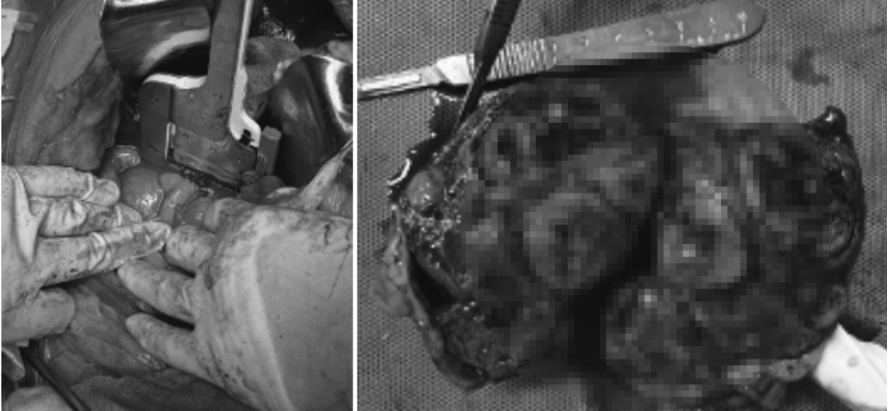

03 간종양 절제 수술 진행 과정

환자는 안정적인 마취 상태를 유지한 후 바로 수술에 들어갔습니다. 수술 중 확인된 사항은 다음과 같습니다.

종양은 간 꼬리엽에 단독으로 발생

|

췌장 및 장간막 일부와 유착되어 있어

매우 섬세한 박리가 필요

출혈 가능성이 있는 부위는 지혈 클립과

지혈제를 이용해 단계적으로 지혈

종양이 포함된 간엽을 완전히 절제

대정맥과 가까운 위치였기 때문에, 수술 과정 전반에서 출혈 관리와 구조물 보호가 매우 중요했습니다.

강아지 간종양 수술사진 / 출처: 에스동물메디컬센터

다행히 수술은 큰 문제 없이 마무리되었고, 회복 과정에서도 특별한 합병증 없이 안정적인 상태를 유지했습니다. 환자는 수술 후 4일째에 퇴원할 수 있었습니다.

이번 간세포암 제거 수술은 울산 에스동물메디컬센터 외과센터 종양외과 특화, 김예은 과장님께서 진행해주셨습니다.

절제한 종양 조직의 검사 결과는 Hepatocellular carcinoma, 즉 간세포암으로 확인되었습니다. 다행히 잘 분화된 타입의 악성 종양이었고 수술적으로는 완전 절제가 이루어졌습니다.

강아지 간종양 조직검사 결과 / 출처: 에스동물메디컬센터

⚠️ 다만, 이미 부분 파열이 의심되었던 병변이 있었기 때문에 복강 내 미세 전이가 발생했을 가능성을 배제할 수 없어 현재는 항암 치료를 병행하며 관리 중입니다.